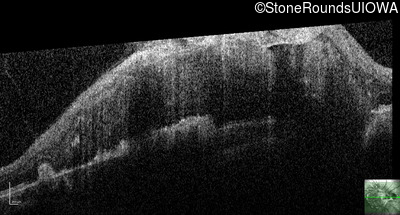

This 9 year old male was noted to have some crossing of his eyes at 2 months of age and the eye exam which followed identified a retinal lesion in the right eye. When he was six years old an epiretinal membrane was noted in his left eye. Two years later it was decided that it was a thin hamartoma in that eye as well. He underwent neuroimaging at age 7 which identified bilateral acoustic neuromas.

| Age at visit: 8 years |

| Age at visit: 10 years |